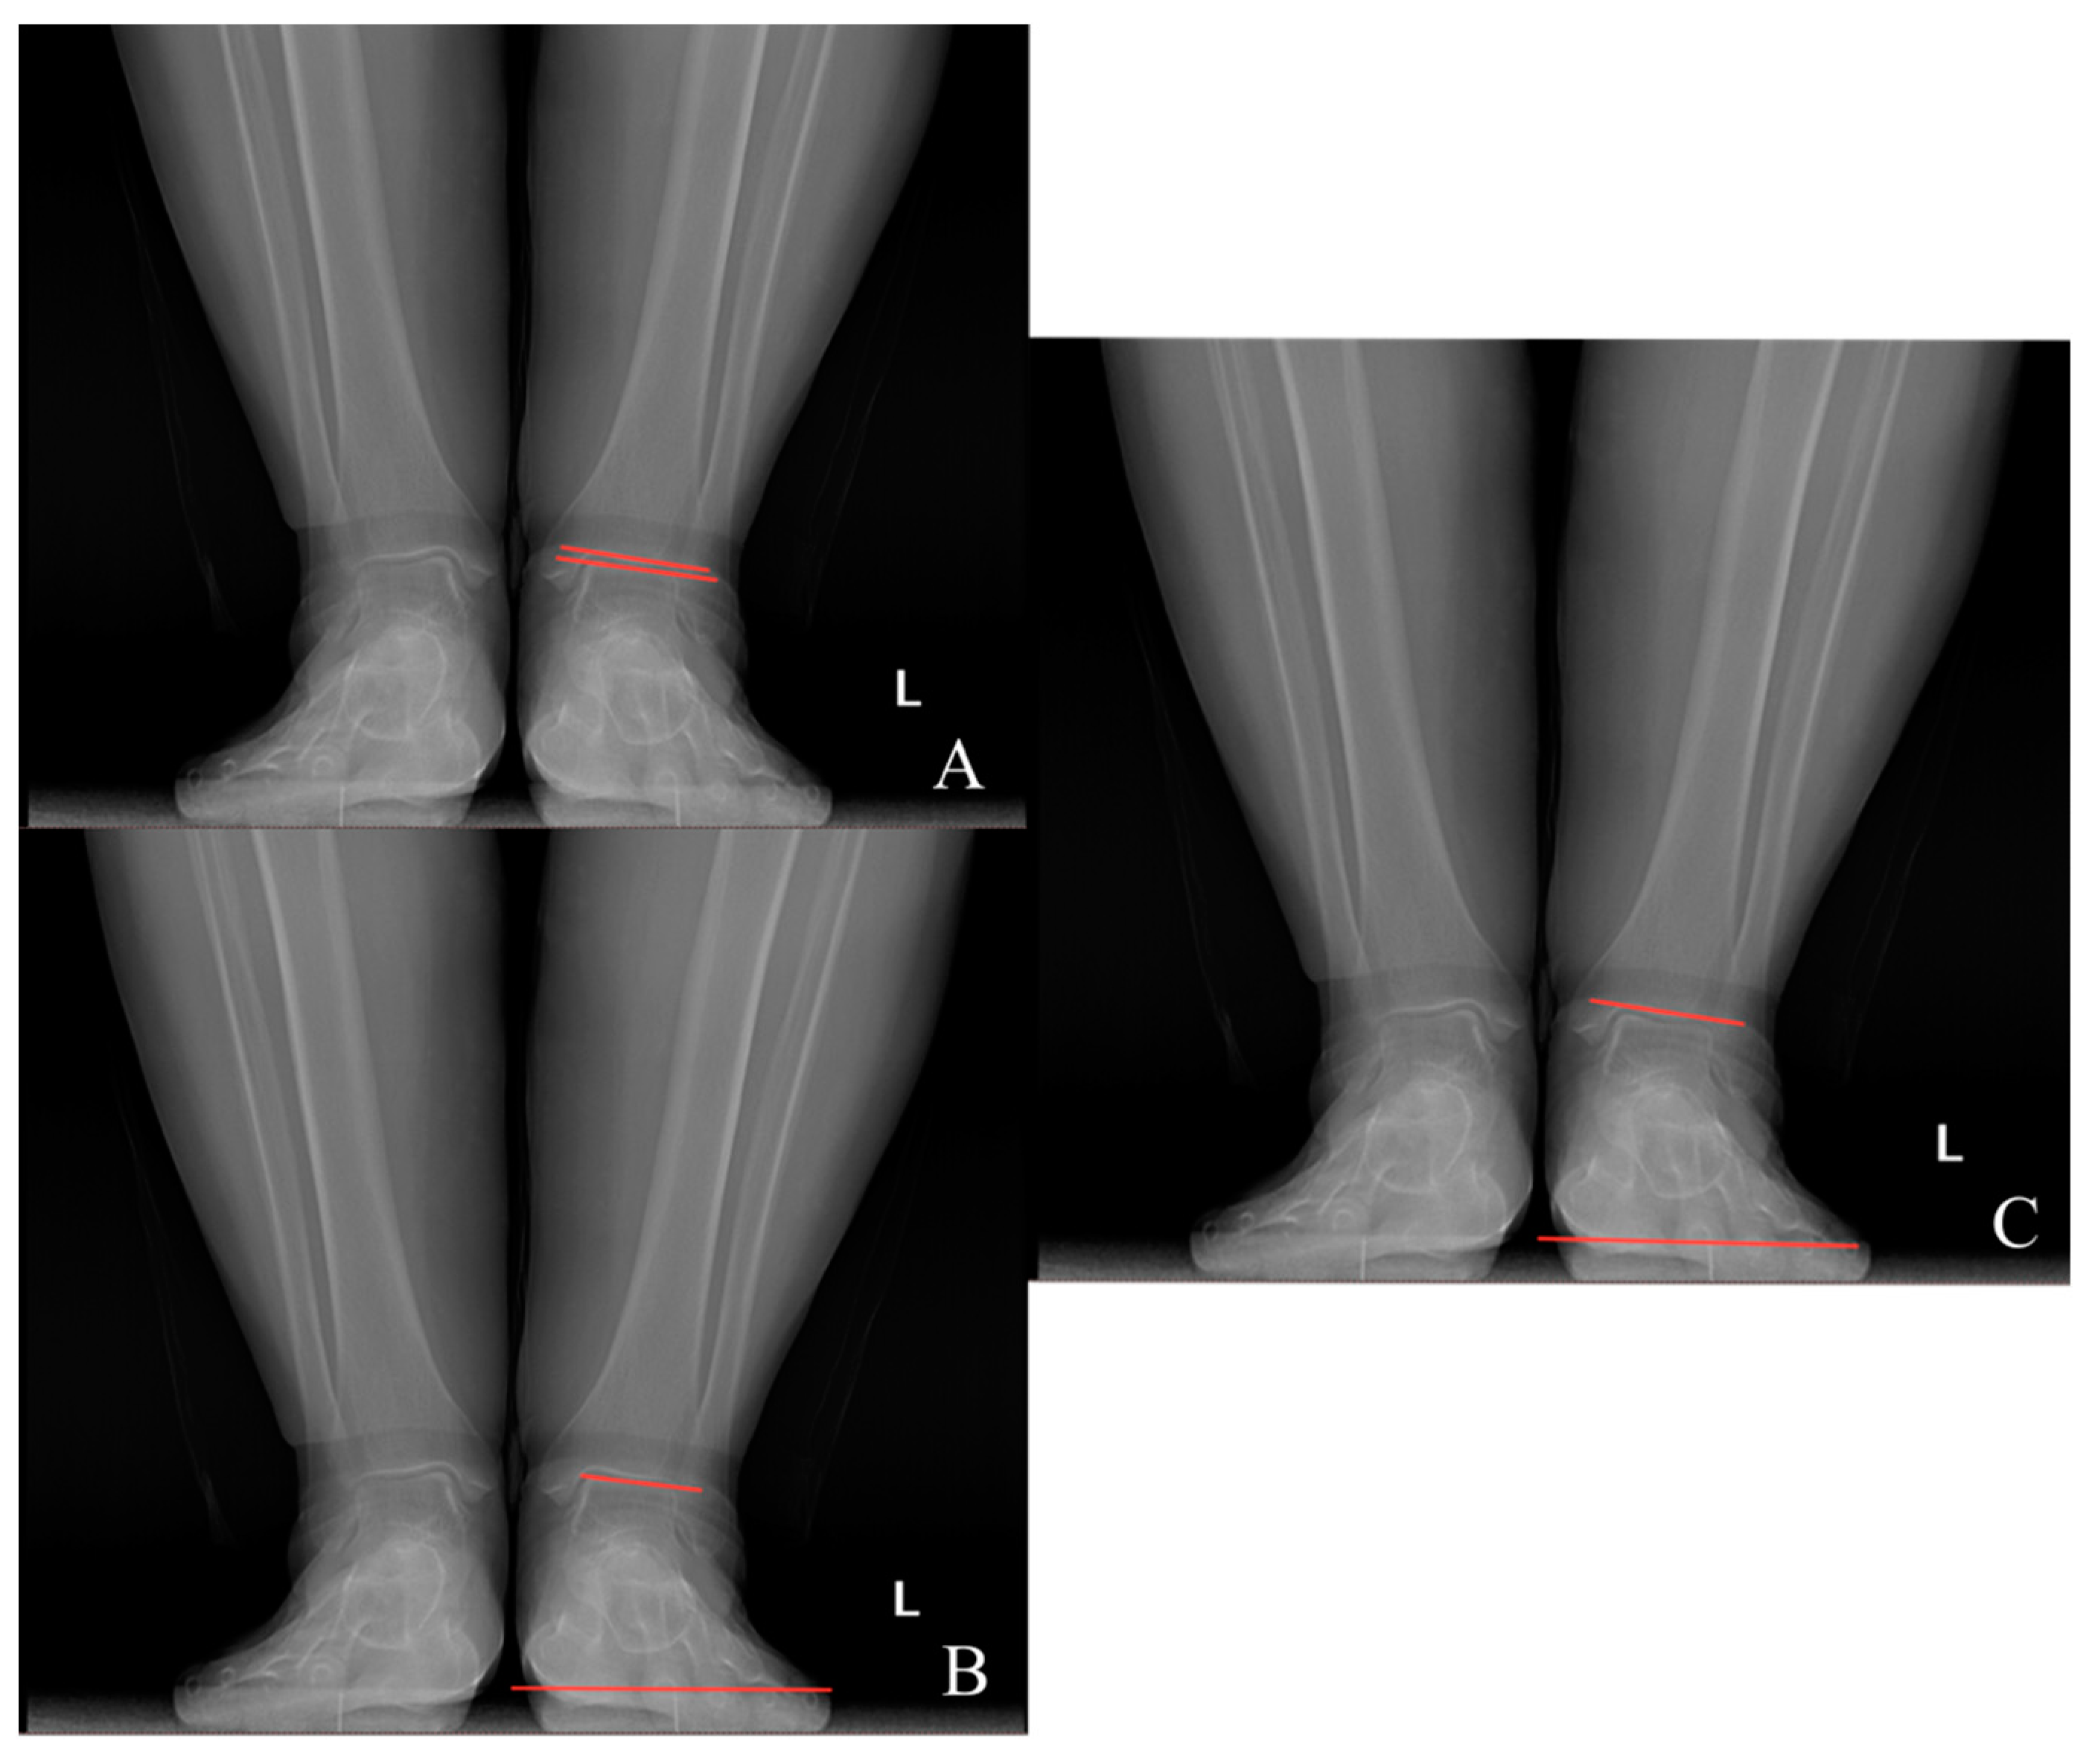

Preoperative and last visit full-leg standing radiographs were evaluated in each patient. Radiological measurements were performed using the picture archiving and communication system software. Two researchers independently measured the selected angles on all radiographs. The study utilized the average of the measured values. The hip–knee–ankle (HKA) angle was defined as the angle between a line drawn from the center of the femoral head to the femoral intercondylar notch and another line from the center of the tibial plateau to the mid-talar dome. The joint line convergence angle (JLCA) was measured as the angle between the femoral and tibial joint lines. The talar tilt (TT) angle was defined as the angle between the subchondral plate of the distal tibial articular surface and the talar dome, with the apex lateral angles positive and the apex medial angles negative. The ground talar dome (GT) angle was between the talar dome and a line parallel to the ground, and the ground plafond (GP) angle was between the subchondral plate of the distal tibial articular surface and a line parallel to the ground, both with apex lateral angles positive and apex medial angles negative.

The HKA, TT, JLCA, GT, and GP angles were measured on the patients’ radiographs (Figure 2 and Figure 3). The preoperative and last visit American Orthopaedic Foot & Ankle Society (AOFAS) scores were evaluated.

Figure 3.

(A) Talar tilt angle; (B) ground talar dome angle; (C) ground tibia plafond angle.